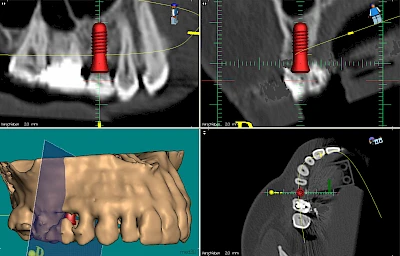

Damit Implantate an der richtigen Stelle im Kieferknochen platziert werden könen, gibt es heute vielfältige Möglichkeiten der Planung. In vielen Situationen kann die Erfahrung des Zahnarztes ausreichend sein.

Nicht selten ist jedoch auch eine technisch aufwändigere Vermessung im Vorfeld sinnvoll, z. B.:

- Wenn sich der Kieferknochen abgebaut hat

- Wenn der Nervverlauf im Unterkiefer beachtet werden muss

- Wenn die Ausdehung der Kieferhöhle im Oberkiefer beachtet werden muss

- Wenn wenige Restzähne keine gute Orientierung erlauben

In diesen Fällen kann die Planung mittels verschieden aufwendiger Röntgen-Techniken (Übersichtsaufnahme, DVT) ggf. unter Zuhilfenahme speziell angefertigter Planungsschablonen sinnvoll sein.